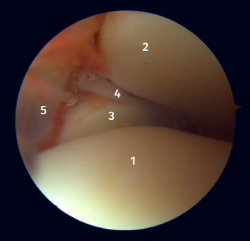

Visión artroscópica posterior

Desde el abordaje posterolateral identificaremos el maléolo peroneo y, desde aquí, visualizaremos las fibras intraarticulares del LTPP, que se dirigen de forma oblicua insertándose en la porción distal de la tibia. También veremos el engrosamiento distal del LTPP (ligamento transverso) en continuidad con el labio posterior de la tibia distal (Figura 4).

Figura 4. Visión artroscópica posterior de un tobillo derecho al que le hemos resecado un proceso de Stieda sintomático. 1: ligamento tibioperoneo posterior; 2: ligamento transverso; 3: cúpula astragalina; 4: tibia distal; 5: articulación subastragalina posterior; 6: flexor largo del hallux.